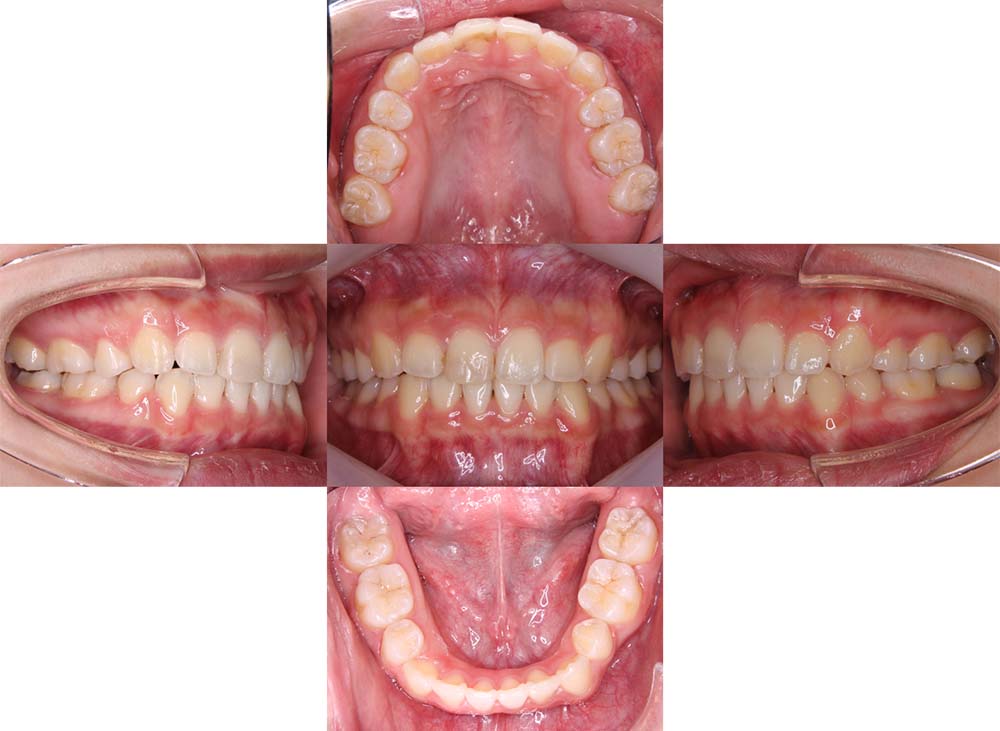

症例02

| 主訴 | 下あご顎が出ている。曲がっている。 |

| 診断名あるいは主な症状 | 反対咬合、非対称、空隙歯列、過蓋咬合 |

| 年齢/性別 | 19歳・女性 |

| 矯正ステージ | 大人の矯正治療 |

| 治療方法 | ワイヤー矯正、顎矯正手術の施行 |

| 抜歯部位/抜歯有無 | 非抜歯 |

| 治療内容 | 上下顎歯列を並べた後に顎矯正手術の施行。 |

| 費用 | 保険治療 |

| 治療期間 | 3年2ヶ月 |

| 主なリスク・副作用 | 痛み、歯根吸収、歯肉退縮、虫歯、後戻り |